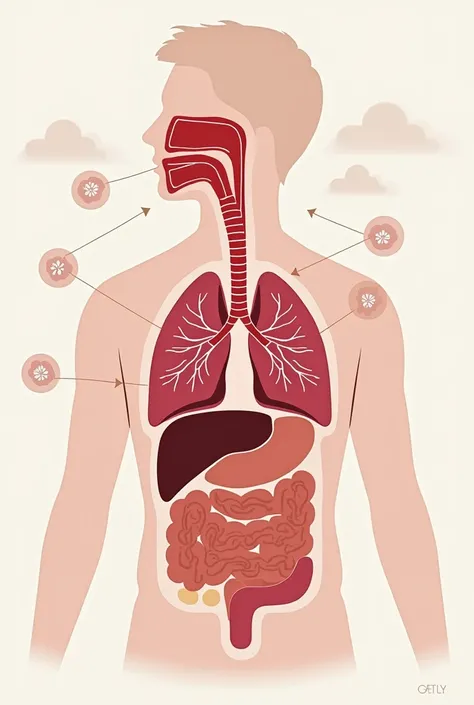

Make a folder about bacterial pneumonia

Make a folder about bacterial pneumonia

Make a folder about bacterial pneumonia